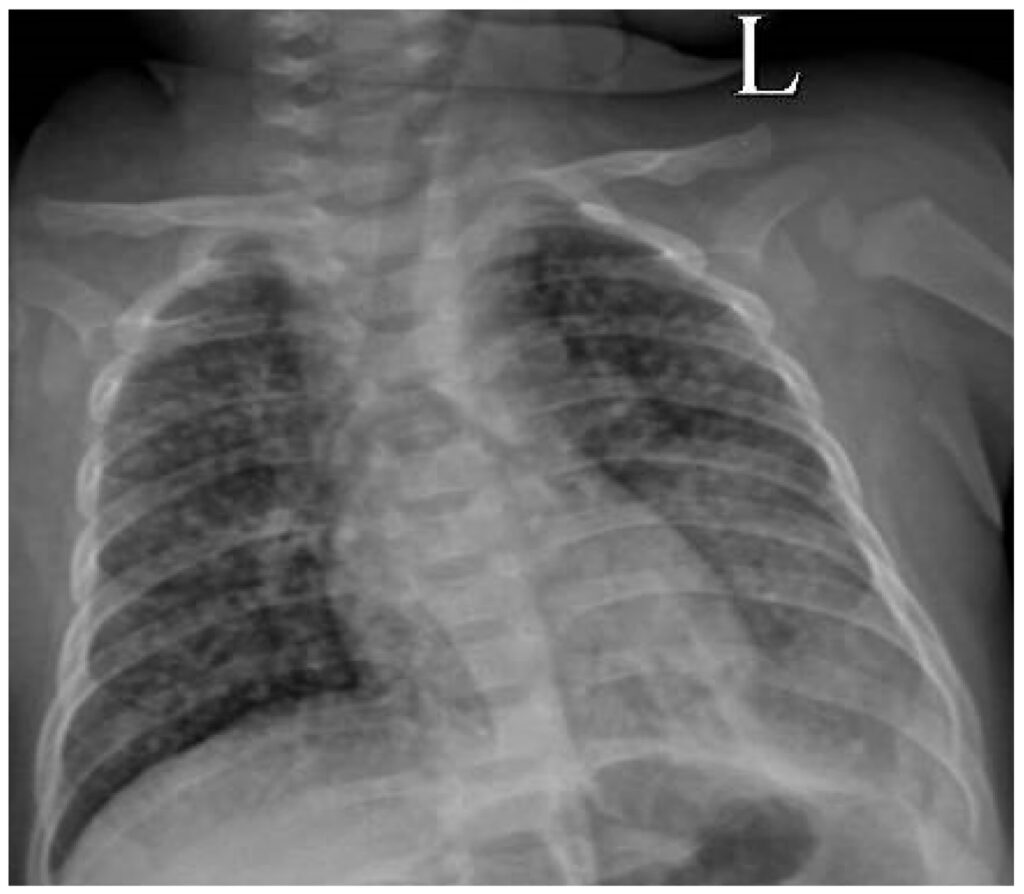

Hvis der er mistanke om bakteriel meningitis forårsaget af meningokokker, kan der tages en podning fra svælget for at undersøge, om patienten er bærer af bakterien. Et røntgenbillede af brystkassen (thorax) kan også være relevant for at lede efter en lungebetændelse, som kan være kilden til en infektion, der har spredt sig til hjernehinderne.